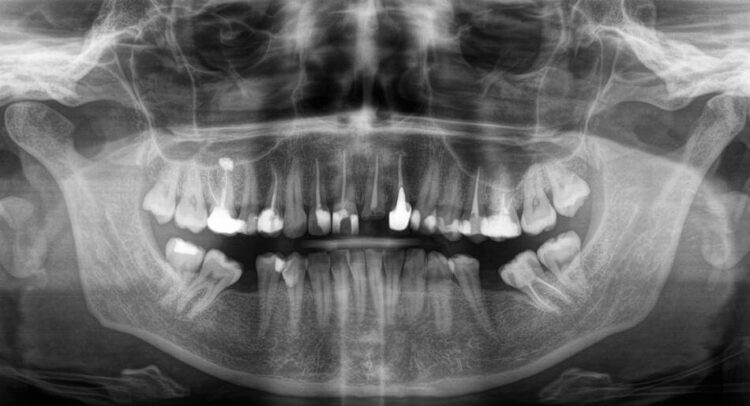

Недавно в нашу клинику с запросом на полную замену зубов верхней челюсти пришла эта же пациентка. Врач провел осмотр и диагностику. Зубные каналы были в норме и не нуждались в лечении. Обнаружены стертые зубы и чтобы визуально их удлинить предложили провести лазерную коррекцию десенного края.

На нижней челюсти отсутствуют шестые зубы, которые нужно заместить имплантами. Поскольку на нижней челюсти будут коронки на импланте, за счет них можно будет поднять прикус и предотвратить стирание зубов в будущем.

В процессе лечения наш специалист предложил внести правки, ведь во время моделирования после получения первичных сканов челюстей было обнаружено, что нижние седьмые зубы сместились в сторону отсутствующих «шестерок». Дефект отсутствующих зубов можно было закрыть с помощью зубных коронок, не прибегая к имплантации, что позволит существенно сократить время и стоимость лечения. Пациентка согласилась на такие изменения в плане и мы продолжили путь к белоснежной улыбке, но без имплантации.